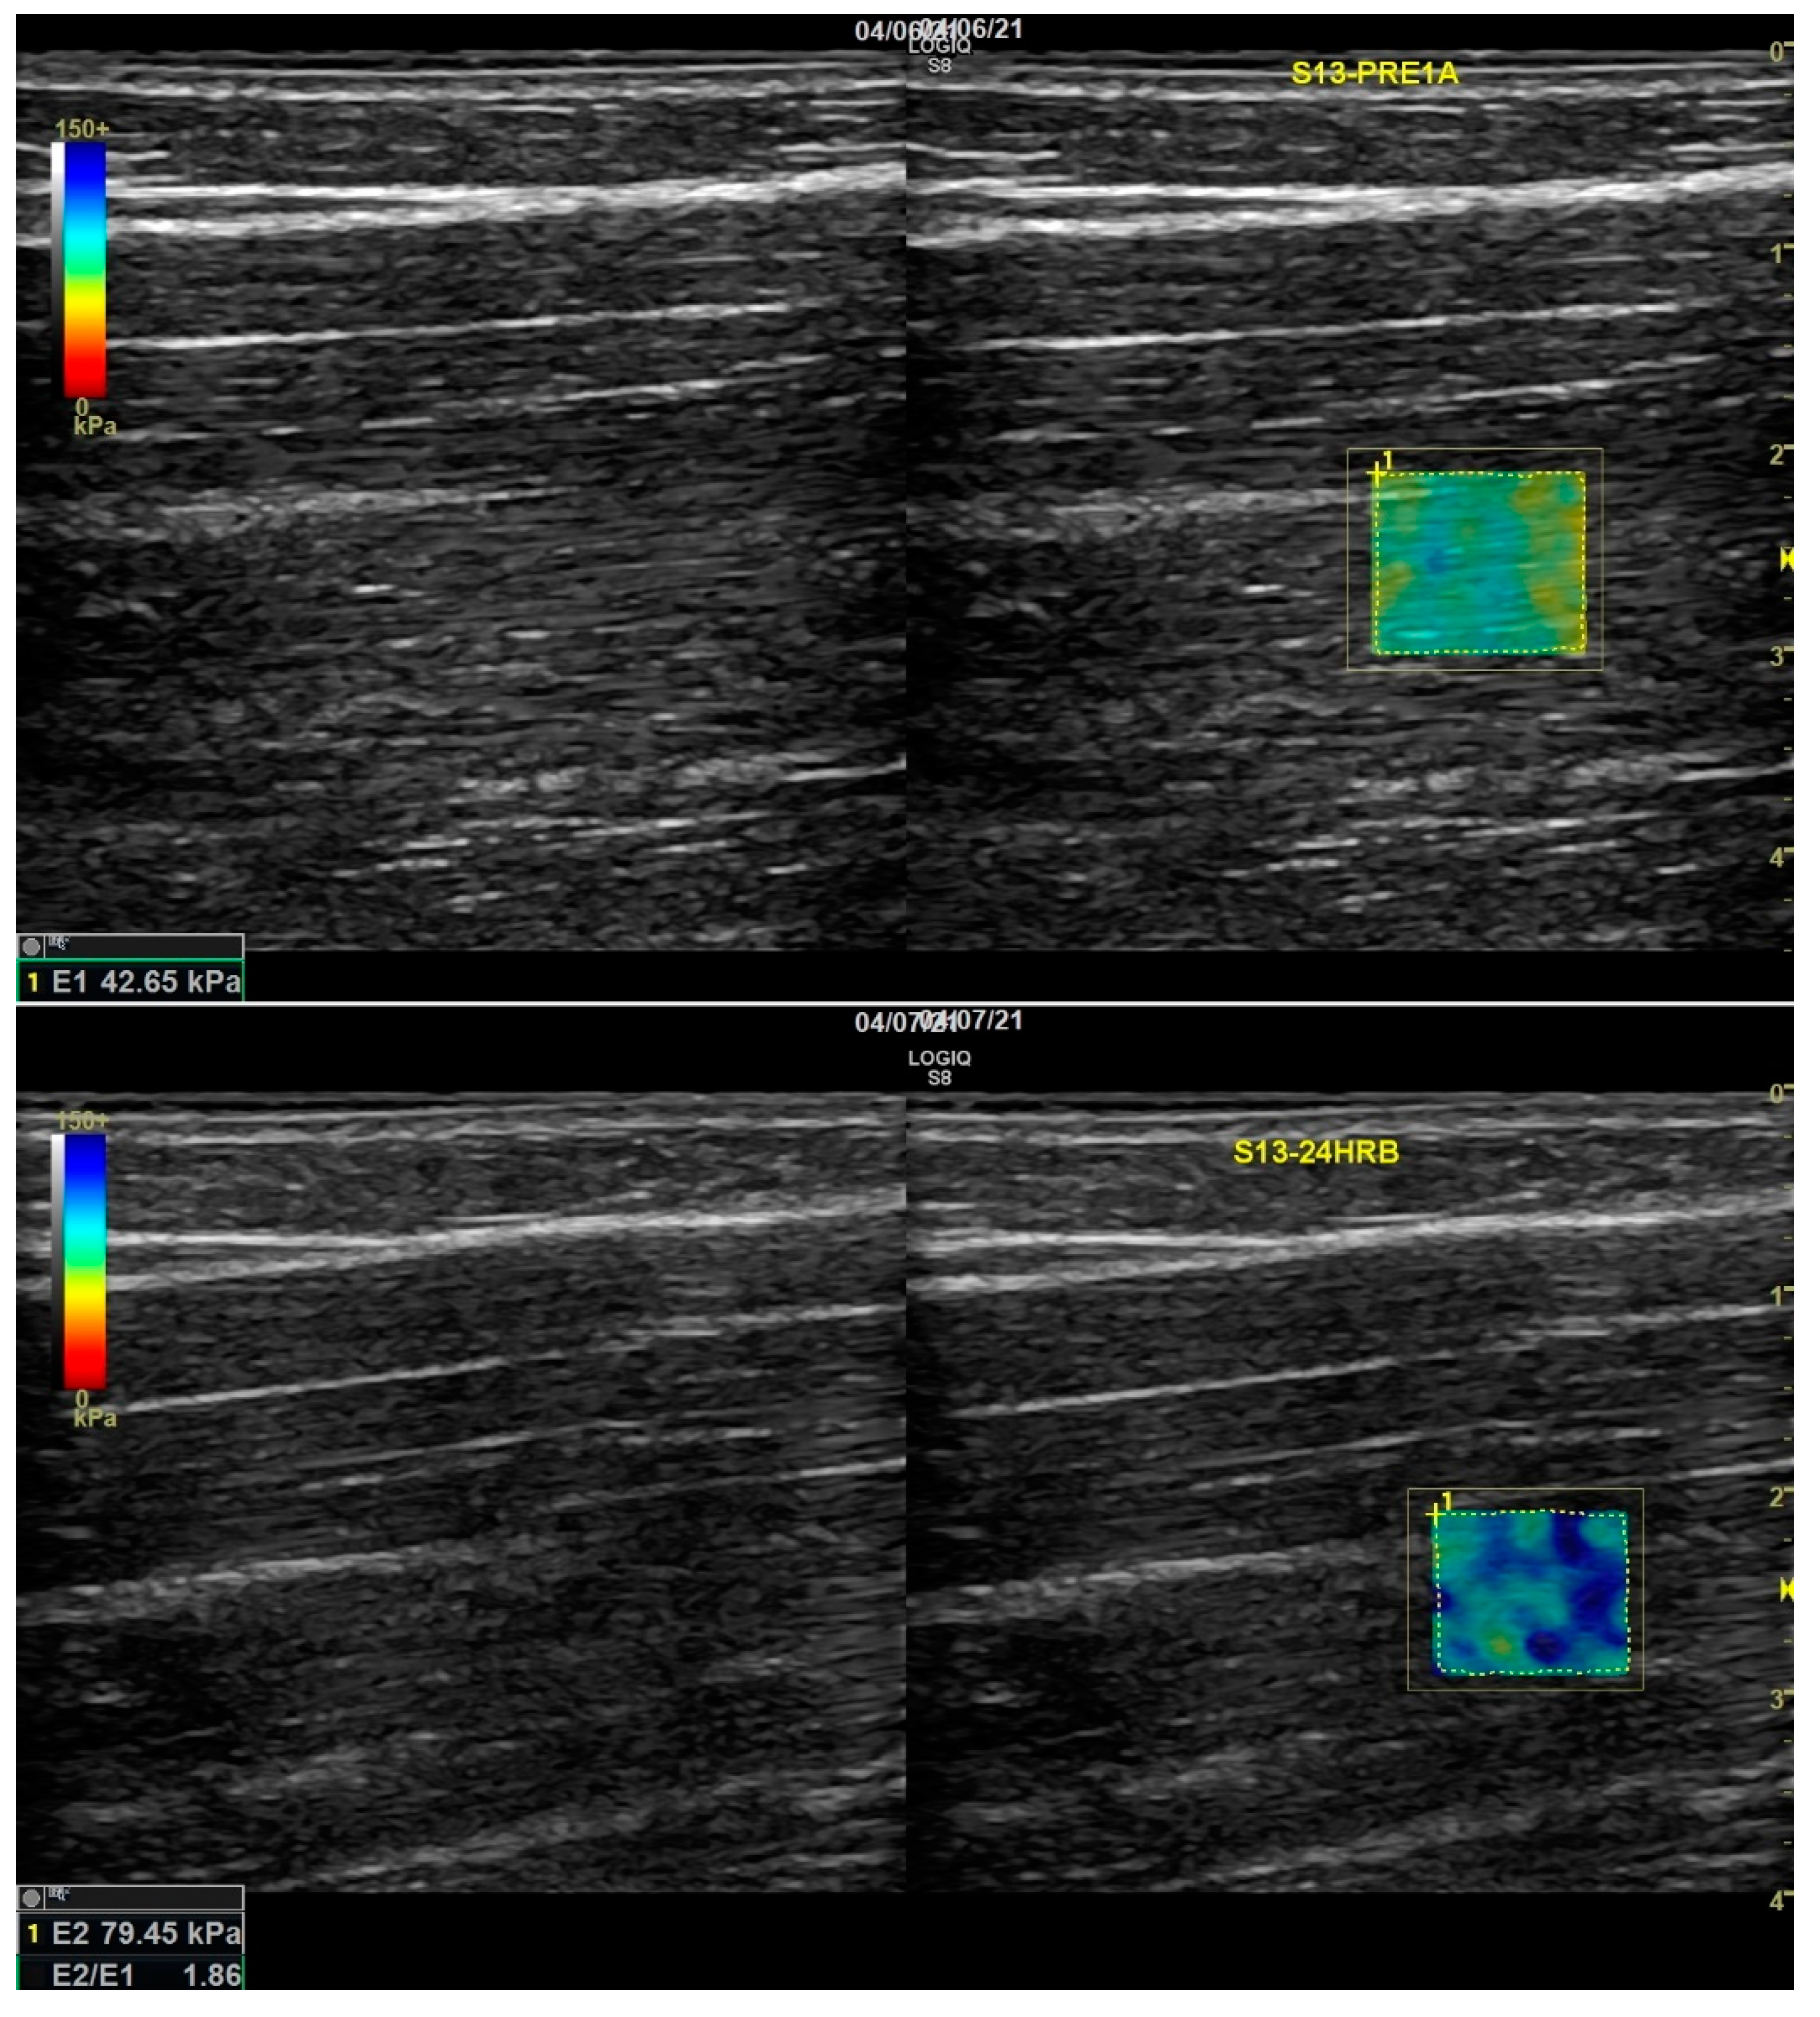

2.5. Shear Wave Elastography (Stiffness)

3.3. SWE (Stiffness)

| SWE | Height | 2.95 | 0.0898 | 0.0258 | C-NV | 14.95 kPa |

| Treatment | 11.97 | 0.0002 | 0.2839 | C-V | 15.83 kPa | |

| Day | 57.92 | <0.0001 | 0.1803 | V-NV | 15.76 kPa | |

| Treatment * Day | 20.17 | <0.0001 | 0.1256 |